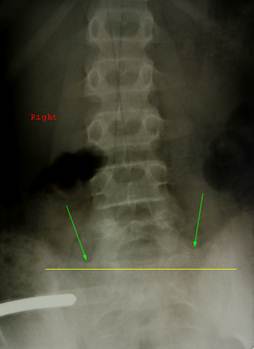

Снимок

таза девочки 15 лет, выполненный по поводу травмы. Хорошо визуализируются ядра

окостенения передних верхних остей и краёв крыльев подвздошных костей. Слева

ядро гребня дошло до третьего сегмента, справа до второго (зелёные стрелки).

Следовательно, признак Риссера равен трём.

Красной стрелкой обозначен перелом нижней ветви лобковой кости слева,

локализованный практически в зоне её слияния с ветвью седалищной кости (их

слияние происходит в возрасте 5 лет).